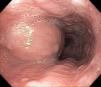

Se realizó una endoscopia de tubo digestivo alto, observándose una lesión ovoidea de 3cm de longitud con mucosa de aspecto normal, localizada a 34cm de la arcada dentaria, con signo de la almohada positivo (fig. 3).